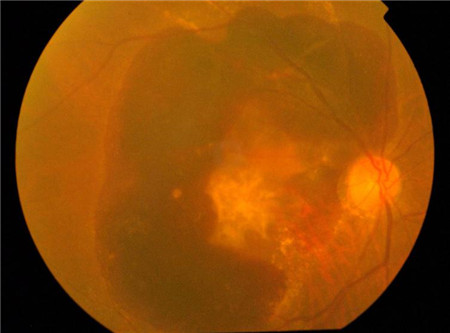

要知道,黃斑變性有干性黃斑變性和濕性黃斑變性兩種情況,干性黃斑變性大多對視力不造成影響。而另一種濕性黃斑病變是因脈絡膜異常增生血管所致,這些不正常的血管很容易發生出血和滲漏,如果不及時進行治療,黃斑區的感光細胞便會被聚集于此的血液和滲出物破壞。若感光細胞受到破壞,視力遭到損害后很難恢復。

大部分黃斑變性的患者屬于干性,由于對視力影響小,一般不需要特殊治療,但需要警惕病情惡化轉變成濕性黃斑變性。對于濕性黃斑變性,北京?,斄猪槼毖劭漆t院主要采取玻璃體內注射抗血管內皮因子藥物的治療方法,也有的患者可能需要結合光動力療法﹑玻璃體注射類固醇及抗血管內皮生長因子藥物三種方法進行治療。

抗血管內皮生長因子藥物治療有助于預防患者視力進一步遭受破壞,在一定程度上還有機會幫助患者改善視力。大部分濕性黃斑變性患者在接受玻璃體內藥物注射治療后,視力可趨于穩定狀態。